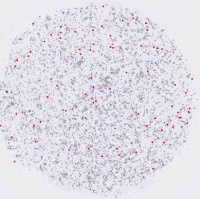

图1

LSIL.